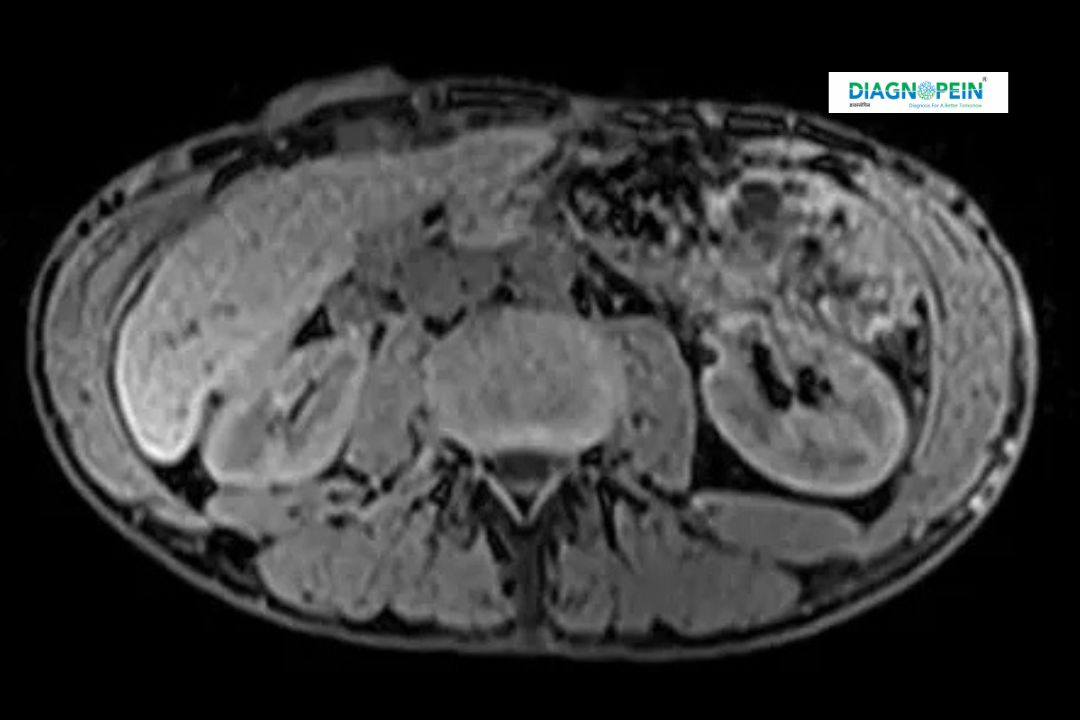

An MRI Abdomen with Contrast is a specialized imaging test that uses magnetic resonance technology and a contrast agent to produce high-resolution images of organs inside the abdominal cavity. This contrast-enhanced technique helps detect conditions that might not appear clearly on standard scans.

At Diagnopein Nanded, advanced MRI scanners are used to examine the liver, kidneys, pancreas, spleen, gallbladder, and other abdominal structures in exceptional detail.

A contrast abdominal MRI scan plays an essential role in identifying abnormalities that non-contrast imaging may miss. The injected contrast material enhances image clarity, highlighting organs, blood vessels, and soft tissues.